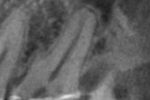

Revisionsbehandlung eines Unterkiefermolaren (37) vor geplanter Überkronung (Dr. Maik Göbbels) Download